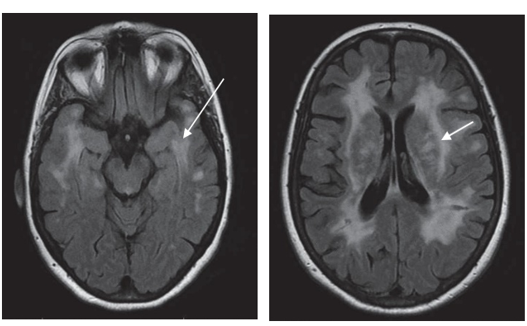

MRI brain scan showing small strokes (indicated by arrow) in CADASIL

A magnetic resonance imaging brain scan (MRI) is usually performed and shows characteristic appearances with abnormalities in the deeper parts of the brain known as the white matter. Involvement of certain brain areas, including a region called the anterior temporal lobe, is a useful guide to the diagnosis. This is a safe scan that involves no radiation but some people find it claustrophobic.

MRI scans of brain: Anterior temporal lobes (left, arrowed) and external capsules (right, arrowed) of the brain